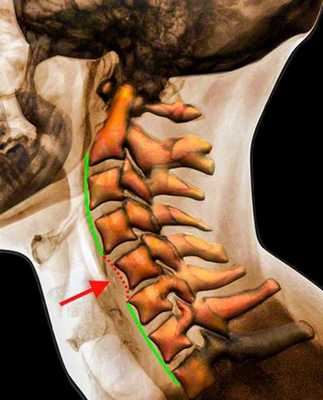

Рентгенограмма. Подвывих в шейном отделе позвоночника. Цветовая обработка изображения.

Половина всех случаев переломов позвоночника приходится на шейный отдел. Многие травмы шейного отдела позвоночника угрожают жизни пациента для жизни пациента. Поэтому они требуют неотложных мероприятий.